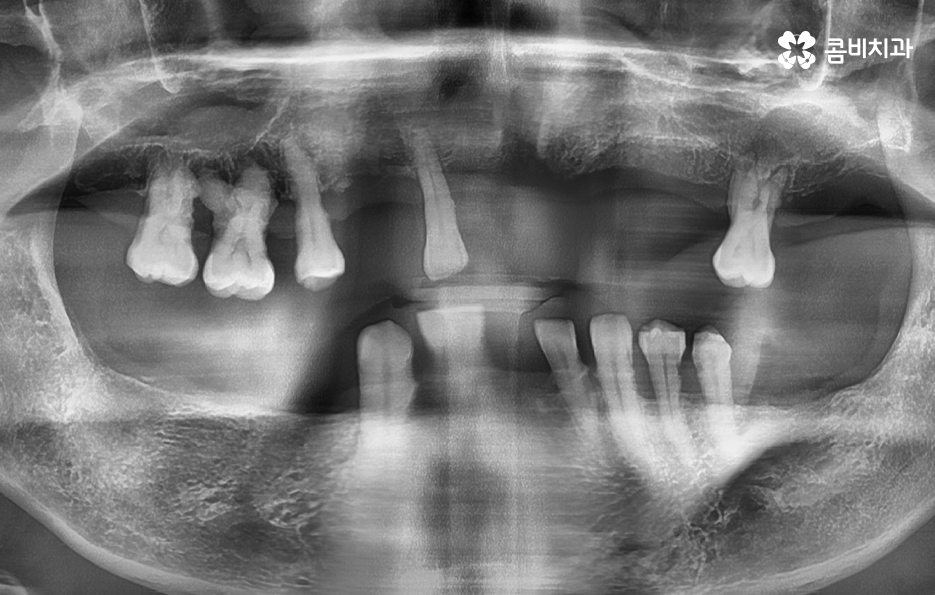

일반적으로 치아는 윗니가 14개, 아랫니가 14개로 이뤄져 있고 나이가 들면서 치아를 하나둘씩 잃다 보면 결국 모든 치아를 잃게 된 상태를 무치악이라고 하며 서너 개씩 없는 경우를 부분 무치악이라고 하고 있어요

보통 젊은 20,30대의 경우 치아를 잃게 되면 그 즉시 임플란트를 하는 경우가 대부분이지만 노년층의 경우 치아를 잃고 방치하다가 틀니를 하는 경우도 있고 치주염으로 치아를 한꺼번에 잃다 보면 임플란트를 하더라도 모든 치아를 수복하는 것이 비용적으로나 잇몸 상태가 좋지 않아서 어려운 경우도 있는데요